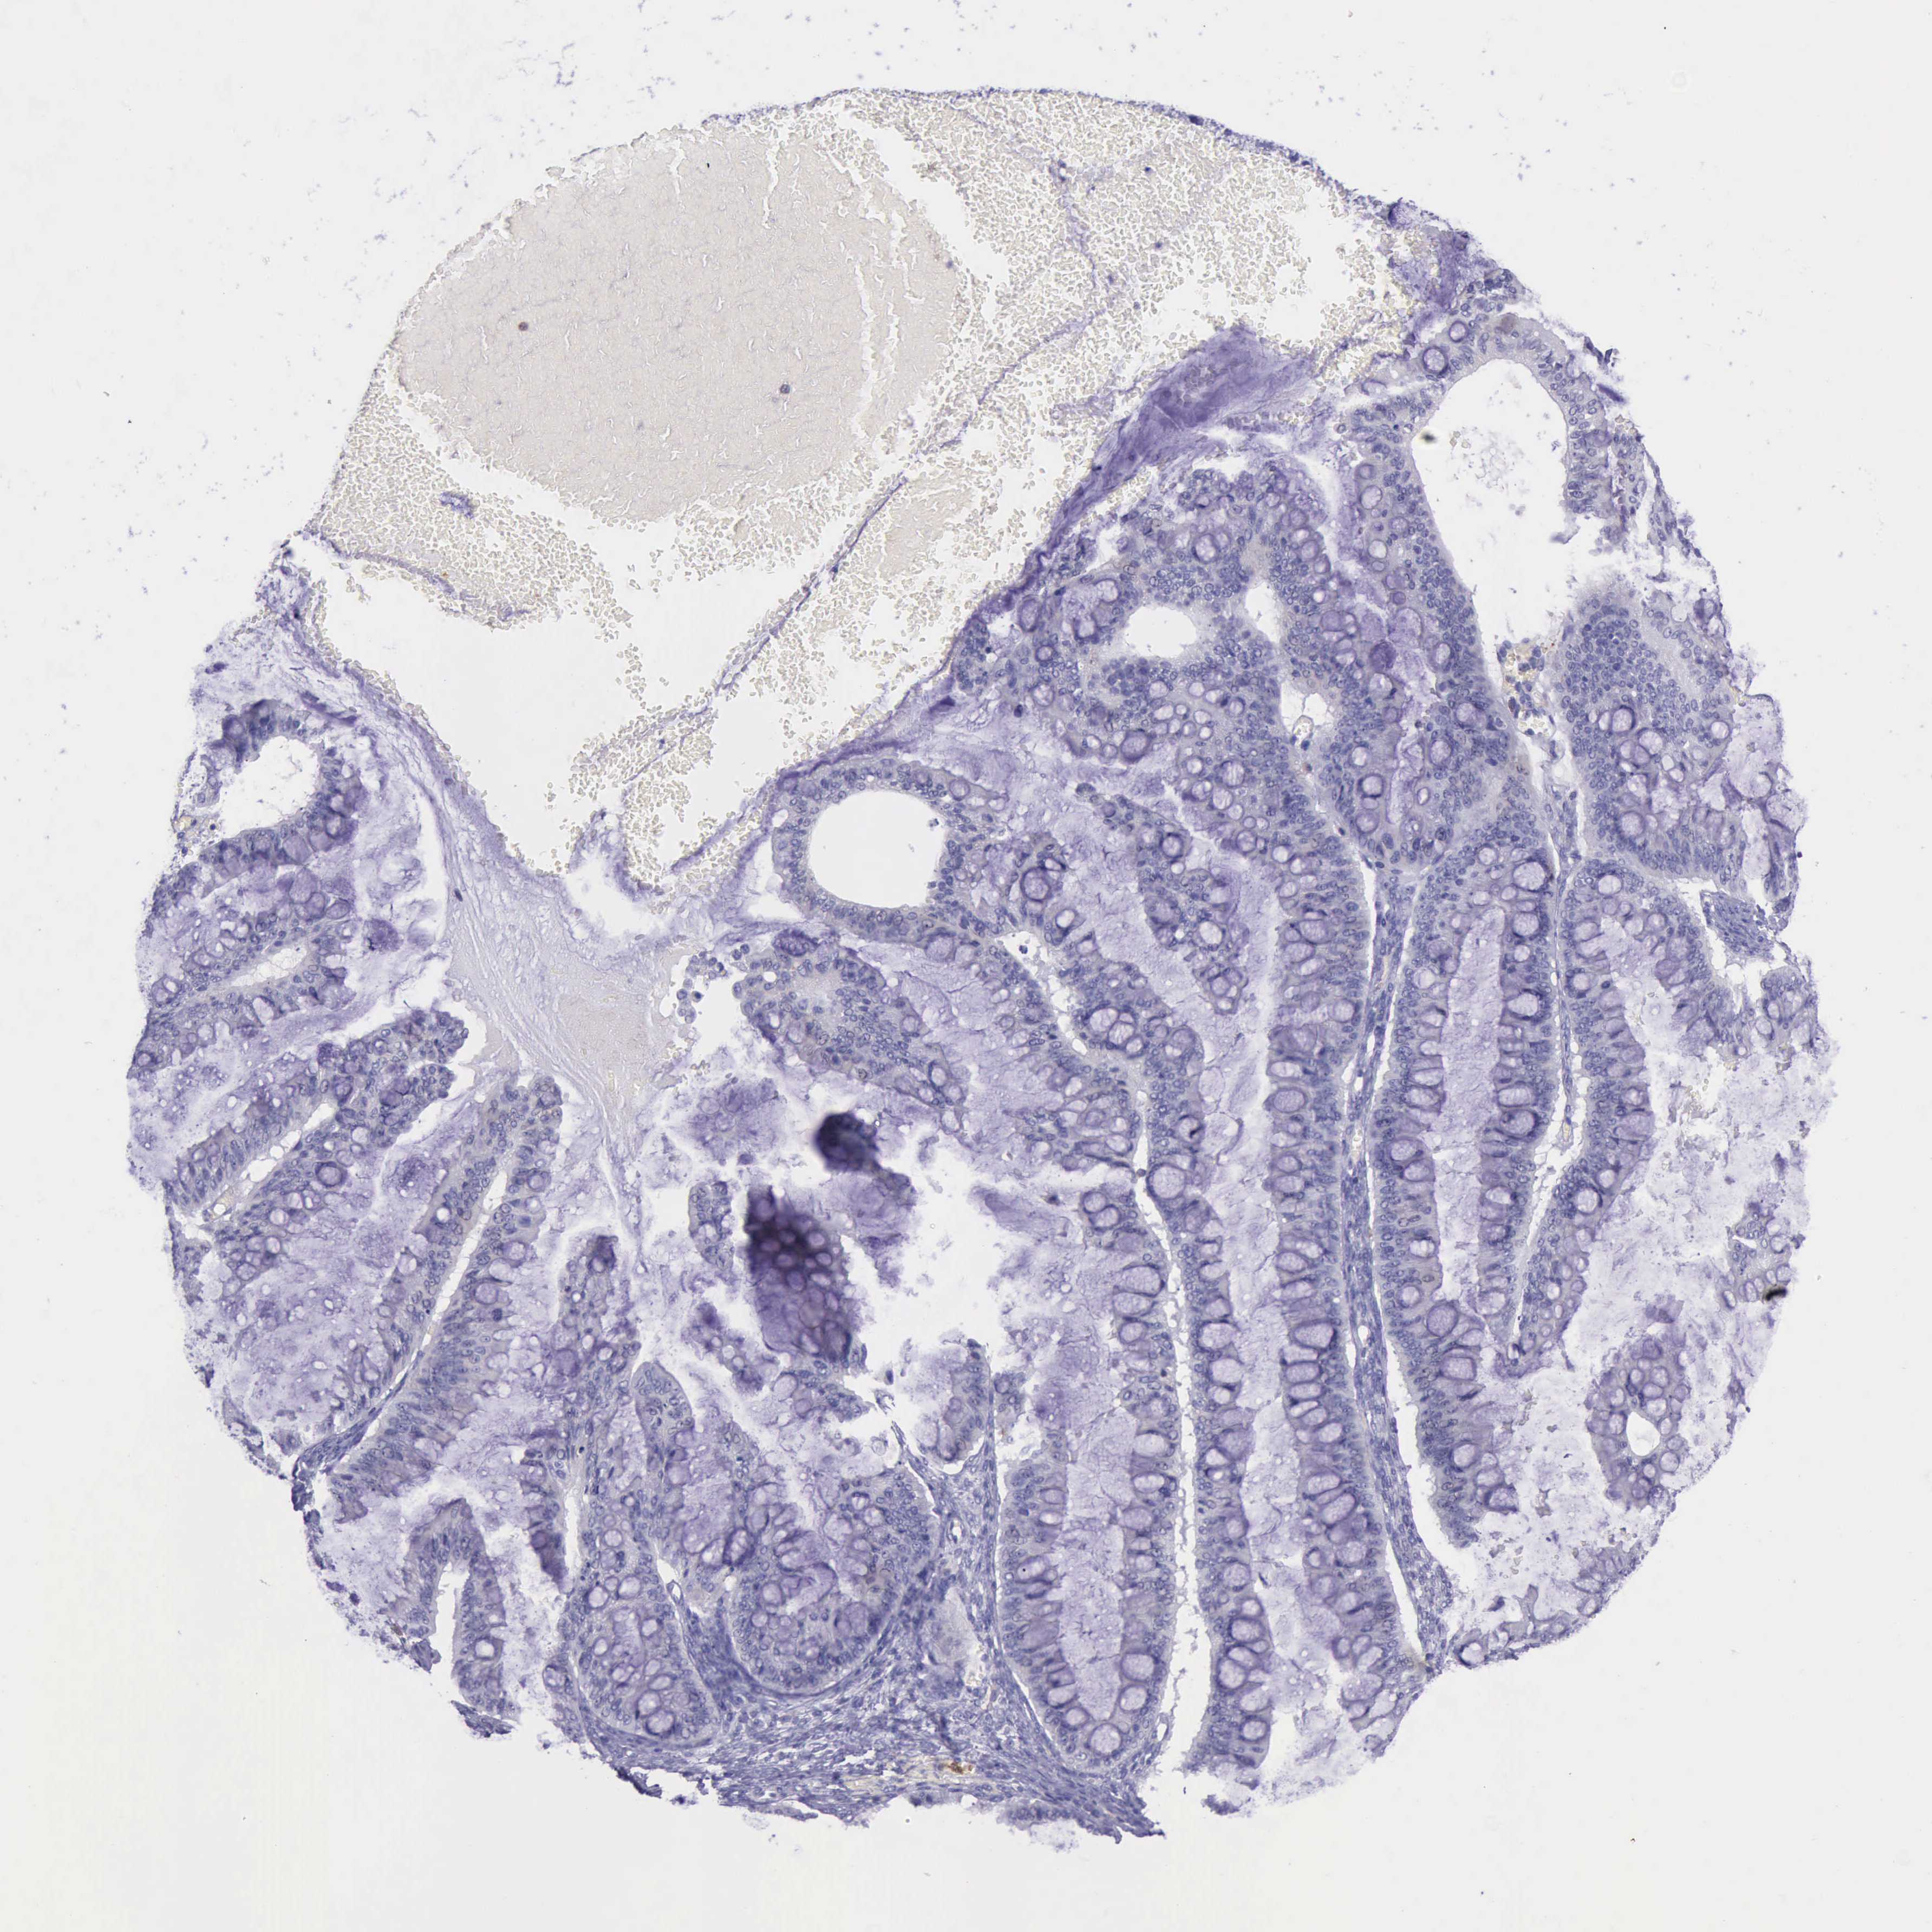

OVARIAN CANCER - Protein expressioni

A mouse-over function shows sample information and annotation data. Click on an image to view it in a full screen mode. Samples can be filtered based on level of antibody staining by selecting one or several of the following categories: high, medium, low and not detected. The assay and annotation is described here.

Note that samples used for immunohistochemistry by the Human Protein Atlas do not correspond to samples in the TCGA dataset.

Antibody stainingi

Antibody staining in the annotated cell types in the current human tissue is reported as not detected, low, medium, or high, based on conventional immunohistochemistry profiling in selected tissues. This score is based on the combination of the staining intensity and fraction of stained cells.

Each image is clickable and will lead to virtual microscopy that enables deeper exploration of all samples and also displays staining intensity scores, fraction scores and subcellular localization as well as patient and tissue information for each sample.

Antibody HPA001198

Antibody HPA002028

Antibody CAB016689

Antibody CAB080300

Cystadenocarcinoma, mucinous, NOS

Carcinoma, endometroid

Cystadenocarcinoma, serous, NOS

Carcinoma, NOS